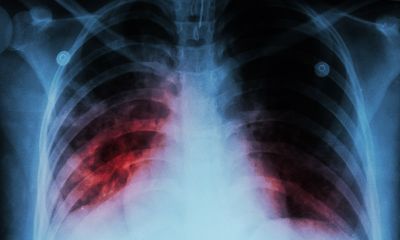

There are over 10 million new cases of TB per year, 600,000 of which were caused by multidrug‑resistant (MDR) strains of Mycobacterium tuberculosis that are resistant to the first‑line drugs of rifampicin and isoniazid1.

More worrying still is the increase in extensively drug‑resistant (XDR) strains that exhibit additional resistance to other classes of drugs. The mechanisms underlying the development of highly transmissible XDR strains are not fully elucidated and studies using short‑ read sequencing technology have limited capacity to resolve the structural variations, gene duplications and repetitive regions which may contribute to resistance, virulence and transmission. To combat these challenges, researchers at The University of Queensland, Australia, are utilising the long sequencing reads provided by nanopore technology to provide a more comprehensive understanding of the evolutionary mechanisms underlying the emergence of highly transmissible strains of M. tuberculosis2.